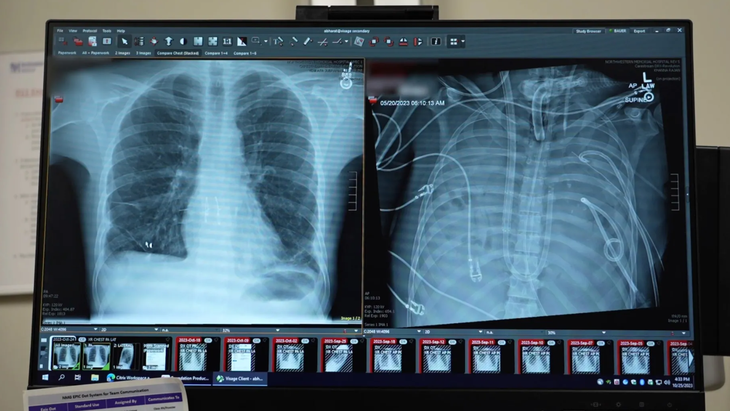

Hình ảnh phổi mới (bên trái) và phổi cũ (bên phải) của bệnh nhân - Ảnh: Northwestern Medicine